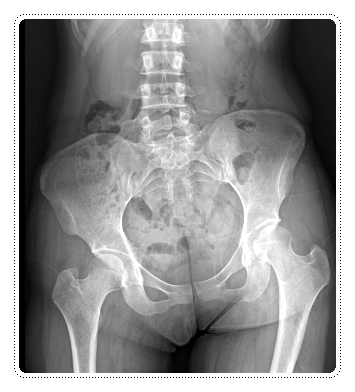

무릎이 아프면 대부분은 ‘무릎 자체’만 문제가 있다고 생각하기 쉽습니다.

하지만 실제로는 허리나 골반, 발목의 균형 문제가

무릎 통증으로 나타나는 경우도 적지 않은데요.

예를 들어 허리에서 신경 자극이 생기면

통증은 무릎 쪽으로 느껴질 수 있습니다.

이런 경우 무릎만 치료하면 잠시 좋아졌다가

다시 통증이 반복될 가능성이 높아지게 됩니다.